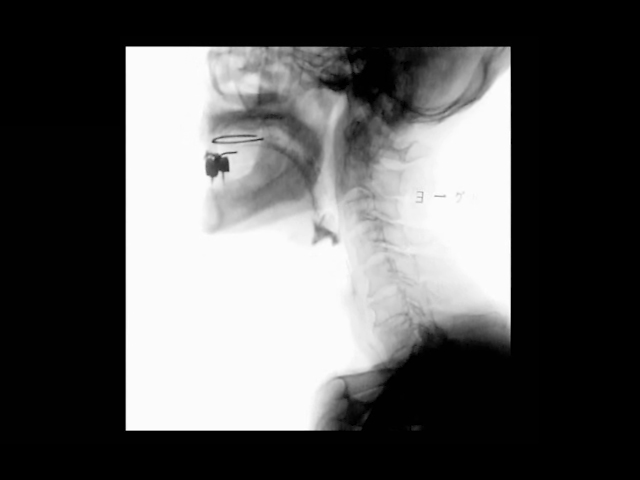

動画2 術後嚥下造影検査